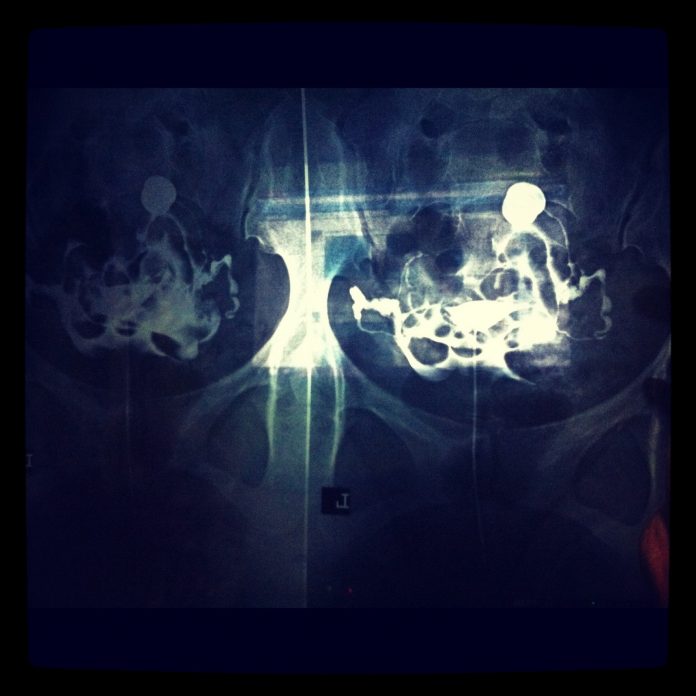

Η κλασική σαλπιγγογραφία (ή υστεροσαλπιγγογραφία) είναι μια μη επεμβατική μέθοδος απεικόνισης των σαλπίγγων.

Συνίσταται στην τοποθέτηση (με ειδικό καθετήρα) ενός σκιαγραφικού υγρού μέσα στη μήτρα. Στη συνέχεια, το σκιαγραφικό προωθείται με πίεση προς τις σάλπιγγες και βγαίνει από αυτές, στην περιοχή της πυέλου της γυναίκας.

Κατά τη διάρκεια αυτής της προώθησης του σκιαγραφικού, λαμβάνονται επαναλαμβανόμενες ακτινογραφίες της πυέλου.